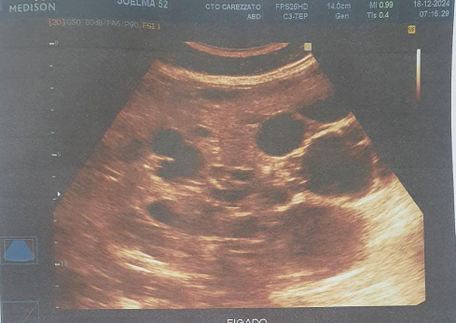

Foi realizado exame de imagem (21/10/2024), ultrassonografia abdominal com os seguintes achados (figura 1.1, 1.2, 2 e 3) Exames laboratoriais (21/10/2024): Acido úrico 2 mg/dl, Bilirrubina total 0,37 mg/dl, Bilirrubina direta 0,18 mg/dl, Bilirrubina indireta 0,19 mg/dl, TGP 21 u/l, TGO 16 U/L, Uréia 34 mg/dl, Creatinina 0,51 mg/dl, Sorologia para hepatite B, C não reagente.

Figura 1.1

Figura 1.1 e 1.2: identificando fígado de contornos irregulares, parênquima heterogêneo, ecogenicidade aumentada, trama vascular diminuída e volume aumentado, múltiplos cistos no parênquima hepático, o maior no lobo esquerdo medindo 8.9 cm x 7.0 cm.